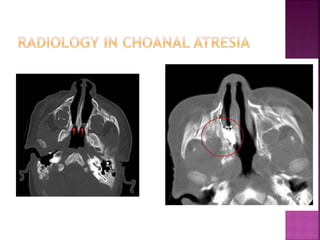

 Partial or complete choanal stenosis

 Unilateral or bilateral

 Obstruction may be bony or cartilagenous

Clinical features :

1. Respiratory distress in newborn

2. RD relieves on crying

3. Cyanosis

 Partial orcomplete choanal stenosis  Unilateral or bilateral  Obstruction may be bony or cartilagenous Clinical features : 1. Respiratory distress in newborn 2. RD relieves on crying 3. Cyanosis